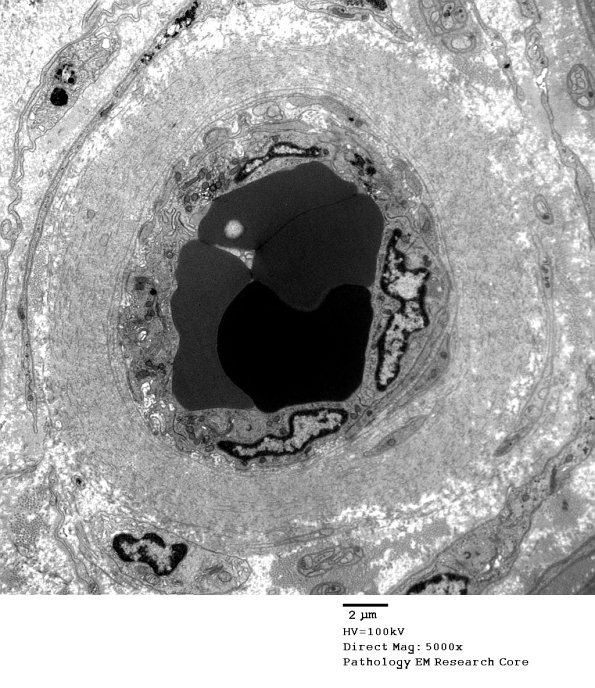

2D1-3 Endoneurial vessel with walls thickened by collagen in longitudinal and circumferential orientation. (electron micrographs)